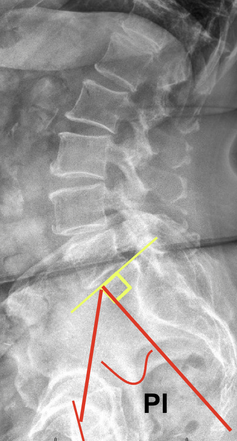

Pelvic Incidence

1) Description of Measurement

Pelvic incidence is a fixed anatomical parameter that describes the shape and orientation of the pelvis. It plays a critical role in determining lumbar spine alignment and overall sagittal balance. PI doesn’t change with posture, it’s unique to each individual, like a fingerprint for pelvic-spinal alignment.

2) Instructions to Measure

• Identify the center point of the femoral heads (use the midpoint if they’re superimposed or draw a line between centers if not).

• Identify the center of the S1 endplate (top surface of the sacrum).

• Draw a line connecting the center of the femoral heads to the center of the S1 endplate.

• Then draw a perpendicular line from the S1 endplate center (pointing upward).

• The angle between these two lines is the pelvic incidence.